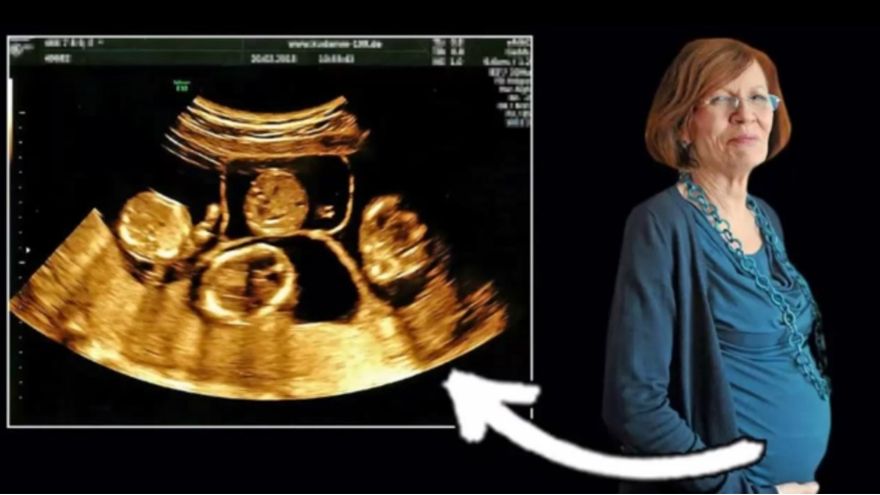

Una profesora de Berlín de 65 años dio a luz a cuatrillizos, indicó el sábado la cadena de televisión RTL, tras un embarazo muy criticado por profesionales de la medicina debido a la avanzada edad de la madre.

Annegret Raunigk dio a luz el martes a una niña —Neeta— y tres chicos —Dries, Bence y Fjonn— por cesárea en un hospital de Berlín, indicó la televisora. Los recién nacidos pesaron entre 655 gramos (1 libra y 7 onzas) y 960 gramos (2 libras y dos onzas) cada uno.

Una portavoz de RTL señaló que los bebés tenían buenas posibilidades de sobrevivir, pero todavía no podían descartarse complicaciones porque habían nacido en la semana 26ta de gestación. La madre se encontraba bien, señaló la portavoz.